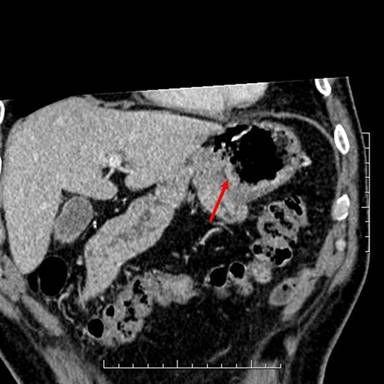

相关图片